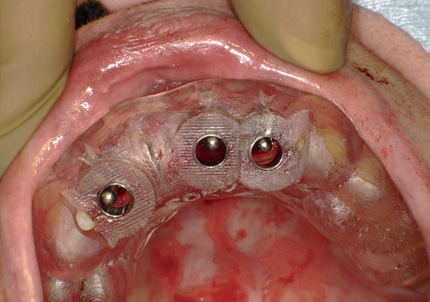

7.サージカルガイドによるインプラント埋入手術

8.テンポラリーヒーリングアバットメント装着して仮歯の作製